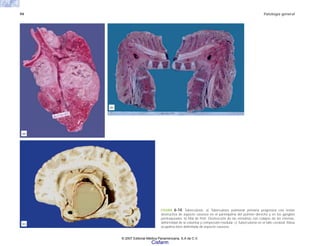

FIGURA 5-2. Anafilaxia experimental en el cobayo. a) Aspecto macroscópico de los órganos torácicos normales; los pulmones están colapsados y retraídos detrás del corazón. b) Órganos

torácicos de un cobayo muerto por choque anafiláctico; los pulmones están sobredistendidos, cubren casi toda la cara anterior del corazón y se ven muy pálidos.